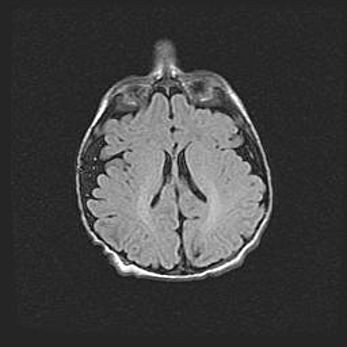

Неполная лизэнцефалия (пахигирия). Открытая гидроцефалия.

Возраст: 17 дней

Вес: 3110 г

Пол: мужской

Окружность головы: 33,5 см

Срок гестации: 35-36 недель

Лизэнцефалия—недоразвитие корковой пластинки и мозговых извилин в результате нарушения миграции нейронов коры. Поверхность мозговых полушарий гладкая. Микроскопически выявляется отсутствие нормальных слоев коры и скопление групп нейронов в подкорковом белом веществе.

Пахигирия—уменьшение числа вторичных извилин. В пораженном полушарии нервные клетки образуют толстый недифференцированный слой с неправильно расположенными нервными волокнами и группами гетеротопных клеток. Нервные клетки незрелые. Белое вещество истончено. При этом нередко аномально развит корково-спинномозговой путь.